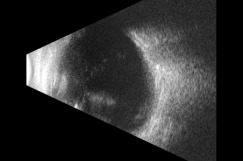

The patient was referred to the retina service for a same-day evaluation. A B-scan ultrasound ruled out a retinal detachment in the right eye (Figure 3). Laboratory testing for inflammatory disease was ordered including Toxoplasma titer, Lyme serology, ACE, serum lysozyme, RPR and FTA-ABS. The results of these tests were unremarkable. The patient was diagnosed with UGH Plus and prescribed topical prednisolone acetate 1% every 2 hours while awake, and cyclopentolate 1% three times a day.